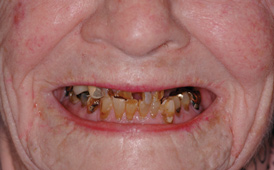

Fig 8. Failing dentition in an 82-year-old patient currently diagnosed with tardive dyskensia.

Figure 8

A patient with tardive dyskensia, for example, may experience dramatic changes in expressive facial activity and corresponding dysfunction in the muscle memory needed to repeat a centric position.19,20 Figure 8 and Figure 9 show an 82-year-old patient who had previously been treated for depression, had a failing dentition, and was diagnosed with tardive dyskensia. Extreme uncontrolled contortions of the facial musculature were evident in the patient when attempting to record a high smile line; removal of enough maxillary bone to hide the transition line was impossible. Dramatic compromises in occlusal scheme may be necessary to achieve even a moderately successful result; yet the implant approach realistically may be the only way to offer any functional improvement (Figure 10 and Figure 11).